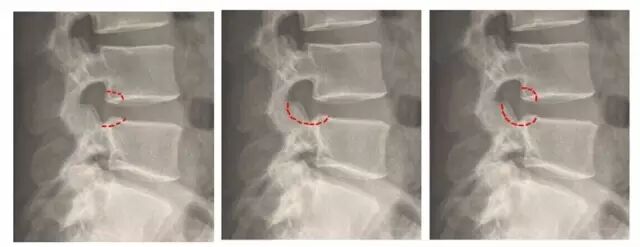

腰椎管狭窄

# l" K- m# B: z" k' h1 Y由于腰椎椎管、侧隐窝、神经根管以及椎间孔的改变,致使骨性结构或纤维结构形态与容积发生异常,单一或多平面中一处或多处管腔内径出现狭窄而引起神经和血管组织活动空间减小,并出现腰骶部或下肢疼痛的临床综合征。

- `& d/ F" v0 N9 {9 N/ t经椎间孔入路内镜下椎管 360 度减压术